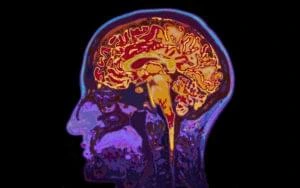

Focused ultrasound is an early-stage, non-invasive therapeutic technology that could transform the treatment of glioblastoma by serving as an alternative to surgery and radiation.